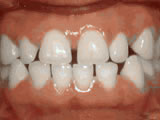

Deep overbite - Lower front teeth bite into palate

deep overbite before

Before

deep overbite after

After

This adult patient, age 25, required braces and jaw surgery to correct his severe overbite, with treatment taking two years. His problem could have been corrected without surgery if he had been treated before he was a teenager.